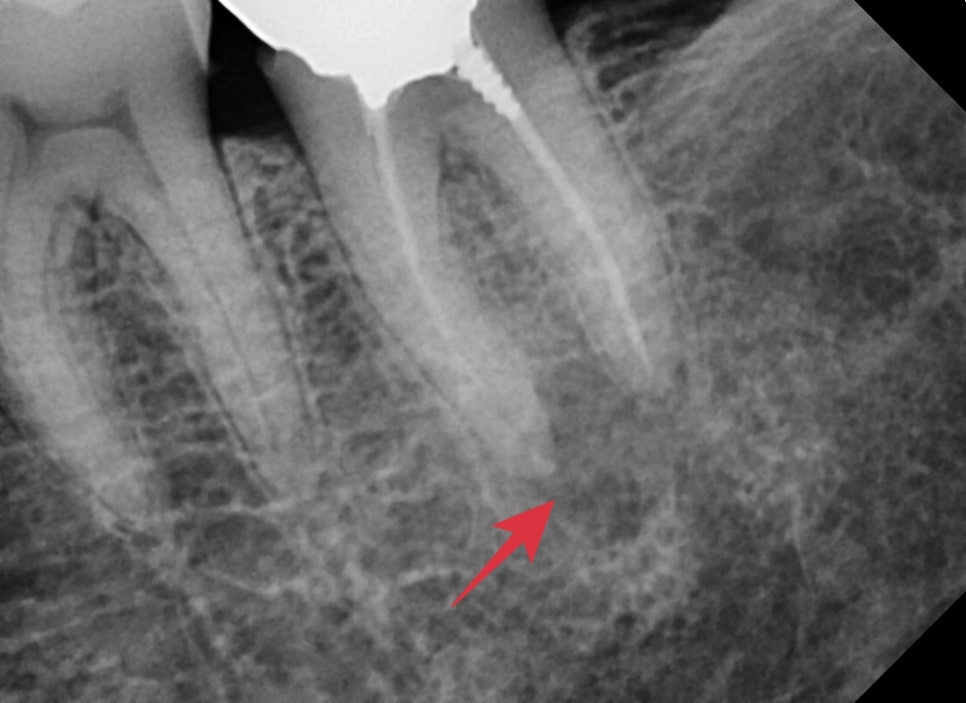

큰 엑스레이상에서 확인할 때 과거에 크라운치료를 받은 치아의 뿌리 주변이 염증소견이 보였습니다.

자세하게 확인하기 위해 해당 치아만 따로 엑스레이 촬영을 했습니다

어금니 뿌리가 4개가 있는데 모두 뿌리 쪽의 염증이 확인되었습니다.

통증이 있던 이유는 염증이 생기면서 압력이 생겨 불편감을 호소하시는 중이었습니다.